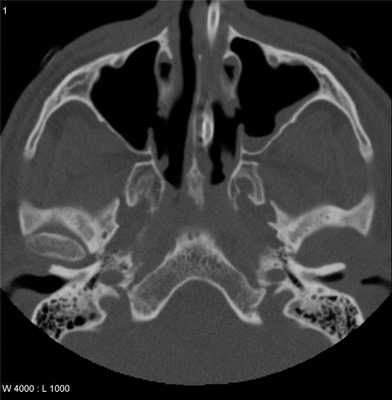

КТ височно-нижнечелюстных суставов, что показывает

КТ височно-нижнечелюстных суставов представляет собой неинвазивный, безболезненный метод диагностики, основанный на способности тканей человеческого тела поглощать рентгеновские лучи с различной интенсивностью. Отличие КТ от рентгенографии заключается в применении специального сканера, способного исследовать челюстно-лицевую область. При этом томограф производит фиксацию изображения послойных тонких срезов (1-2 мм), которое транслируется на экран компьютера, где, при необходимости, реконструируется 3D-модель обследуемой зоны.

Изучение височно-нижнечелюстных суставов (ВНЧС) при помощи рентгеновского аппарата не дает полной информации об особенностях строения и структуры суставных поверхностей. Использование в дифференциальной диагностике компьютерной томографии повышает эффективность обследования. Интенсивность излучения при КТ височно-нижнечелюстных суставов гораздо ниже, что делает этот метод практически безопасным. Но специалисты рекомендуют проходить обследование только по назначению врача, это снизит риск негативного влияния рентгеновских лучей на организм человека.

Что покажет КТ височно-нижнечелюстных суставов

Качественное обследование челюстно-лицевой области помогает выявить ряд нарушений, которые являются признаками серьезных заболеваний. Метод КТ особенно эффективен в диагностике новообразований, показывая незначительные изменения в строении, структуре тканей исследуемой зоны.

Благодаря сканированию в аксиальной проекции, КТ височно-нижнечелюстных суставов позволяет воссоздать форму костных суставных поверхностей, оценить состояние сочленения и прилегающих тканей.

Патологические состояния височно-нижнечелюстного сустава сопровождаются специфическими рентгенологическими симптомами, которые отчетливо видны при КТ:

анкилоз - суставной отросток челюсти соединяется с височной костью посредством соединительной ткани, в этом случае на снимке отсутствует участок пониженной плотности, соответствующий суставной щели;

уплощение - потеря конгруэнтности (соответствия) суставных поверхностей, свидетельствует о наличии дегенеративных патологических процессов;

остеофиты - разрастания костной ткани вследствие деструктивных изменений суставного хряща;

субхондральная киста - полость, образуемая вследствие растворения костной ткани суставной головки, округлая, с четкими границами.

КТ височно-нижнечелюстных суставов в трех взаимно перпендикулярных проекциях дает возможность воссоздать достоверную 3D-модель, где будут отражены малейшие изменения суставных элементов, свидетельствующие о развивающихся патологических процессах.